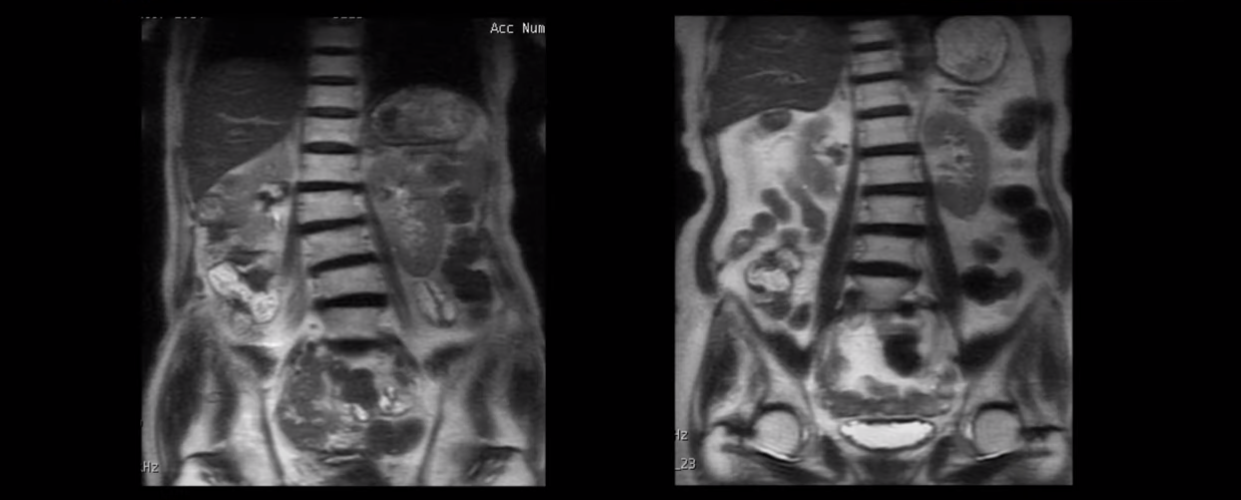

근육이 늙는다는 건 나이가 들면서 근육이 줄어들며 약해지고, 또 이런 근육 상태로 일을 하고 운동을 하니까 결국 근육이 망가지고 뭉치고 뒤틀린다는 걸 말합니다. 그래서 70대 이상 협착증 환자를 척추를 보면 척추가 반듯한 분이 단 한 명도 없습니다.

전부 다 척추가 틀어지고 심하게 휘어져있습니다. 허리 주변 근육이 다 뒤틀려있다는 얘기입니다.

보시다시피 근육도 많이 줄어들어 심하게 작아져 있습니다. 이게 바로 근육에 심한 문제가 있다는 증거입니다.